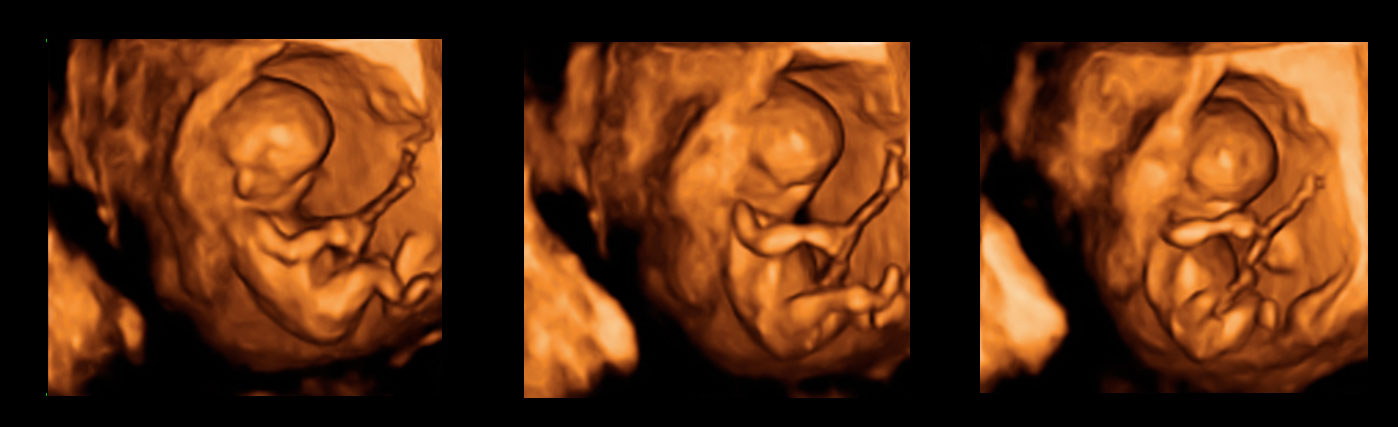

Ecografía Embarazo 2D y 3D Semana 12 - CRIBADO DEL PRIMER TRIMESTRE